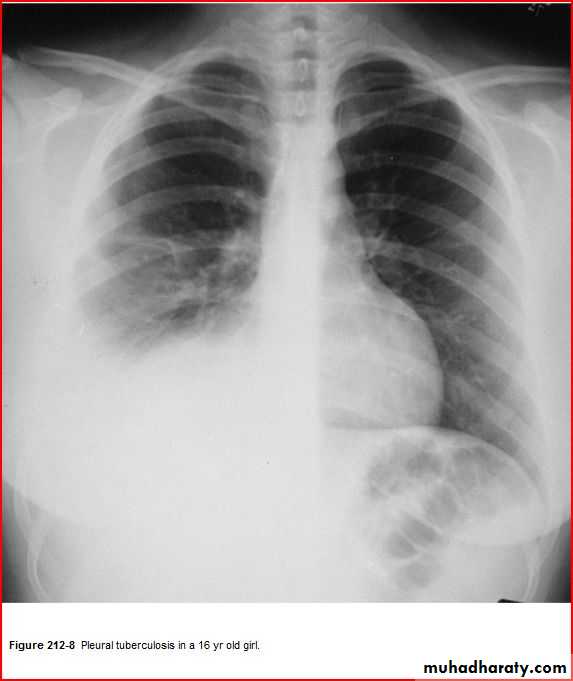

Pleural effeusion + minscal sign

TBPleural effusion meniscal sign